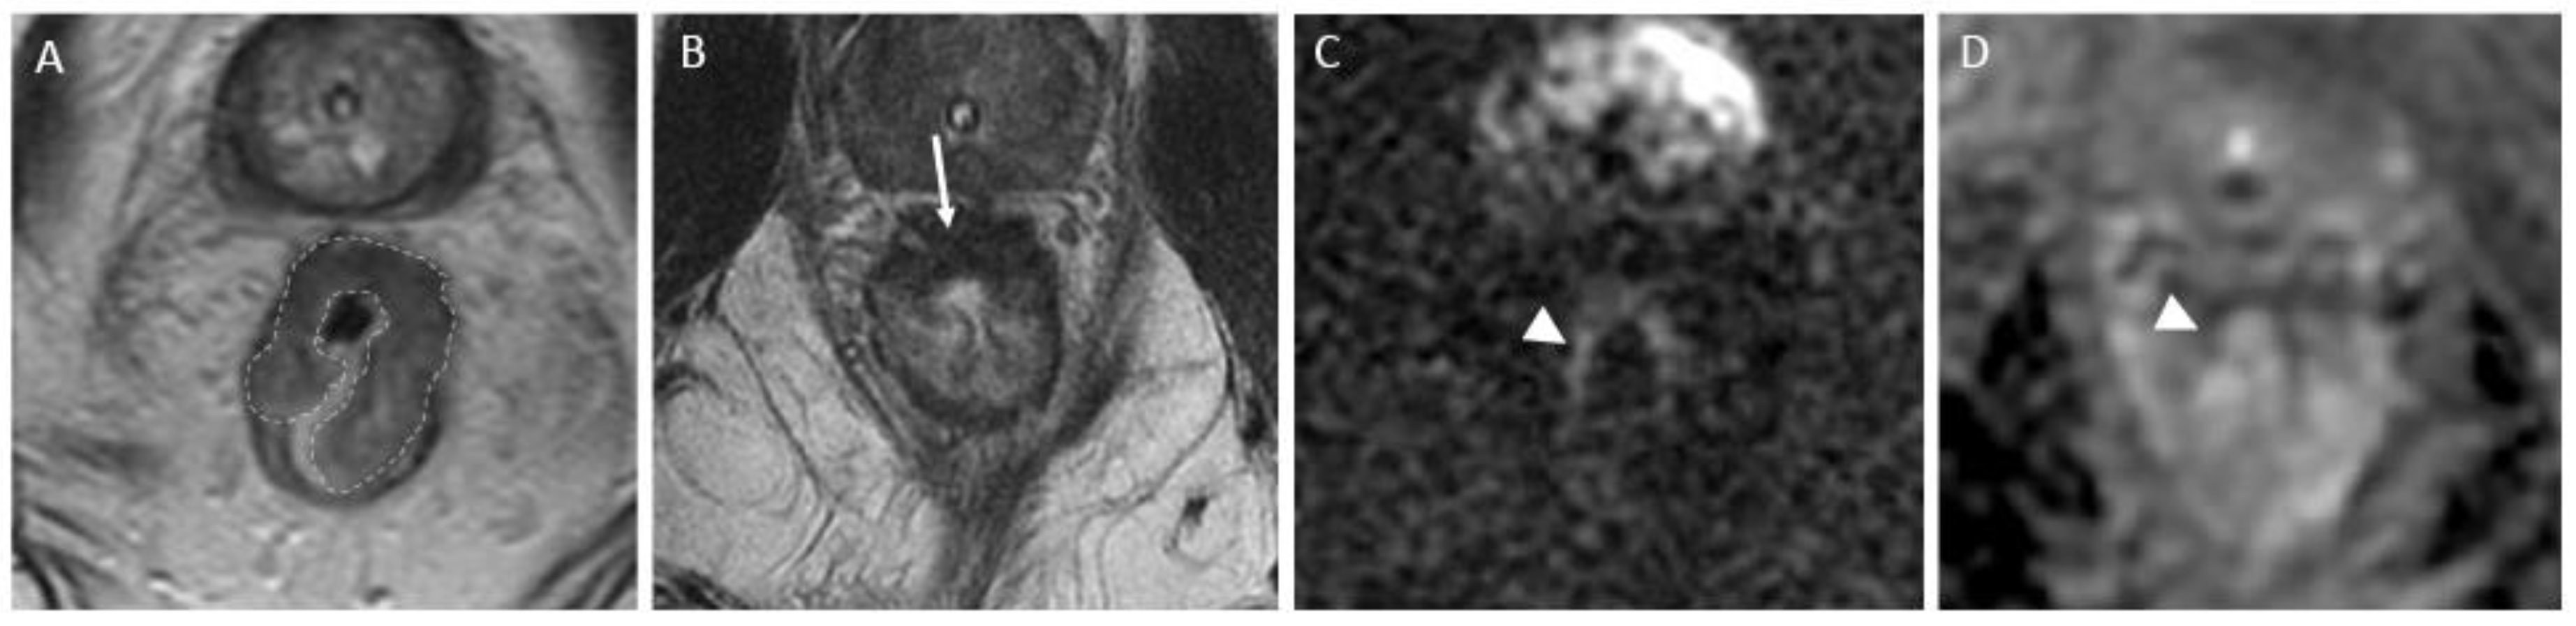

c) iCR characterizes a scenario where tumor volume experiences a reduction, but discernible residual tumor persists. This response type manifests through persistent diffusion restriction and the persistence of T2 intermediate signal within the tumor bed (Figure 4).

Figure 4. Incomplete response in a 60-year-old man with low/middle rectal adenocarcinoma. (A) Baseline axial T2-weighted MR image shows an intermediate-signal-intensity, near-circumferential low rectal tumor (dotted line). (B) Axial T2-weighted MR image after completion of neoadjuvant chemoradiotherapy persistent intermediate signal intensity (arrow), representing incomplete response and residual tumor. (C) Axial diffusion-weighted image shows high signal intensity (arrow). (D) The residual malignancy was identified at endoscopy. The patient underwent total mesorectal excision.